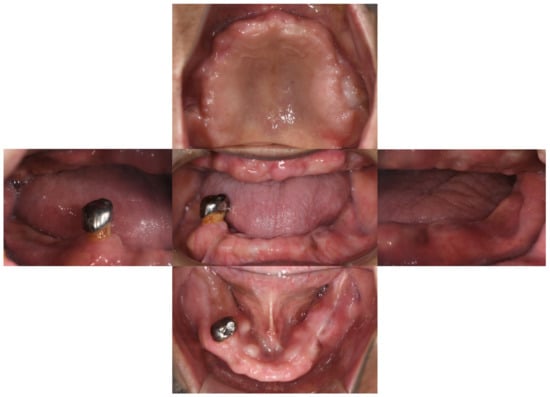

Intra-oral examination revealed maxillary total edentulism and mandibular partial edentulism with only the lower right second premolar remaining (Figure 1). The bony prominence around the bilateral tuberosity areas significantly reduced the space of the retrozygomatic fold. The bony prominence around the mandible extended from the lingual frenum to the retromylohyoid fossa bilaterally (Figure 2). Mild bony prominence was also present around the labial aspects of the maxilla and mandible, making it difficult to distinguish the peripheral frenula.

The morphology of both the maxillary and mandibular edentulous ridges hindered the proper extension of the denture bases. Although surgical removal of the exostoses was suggested, the patient rejected preprosthetic surgery due to personal preference. According to the classification system for complete edentulism, prosthodontic techniques of a specialized nature must be used to achieve an adequate result in such Class IV cases [11].

Figure 2. (Left). The maxillary study model. The bony exostoses around bilateral tuberosity areas hindered the proper extension and the peripheral seal of the maxillary denture. (Right) The mandibular study model. The lingual bony exostoses extended from the lingual frenum to the bilateral retromylohyoid fossa area.